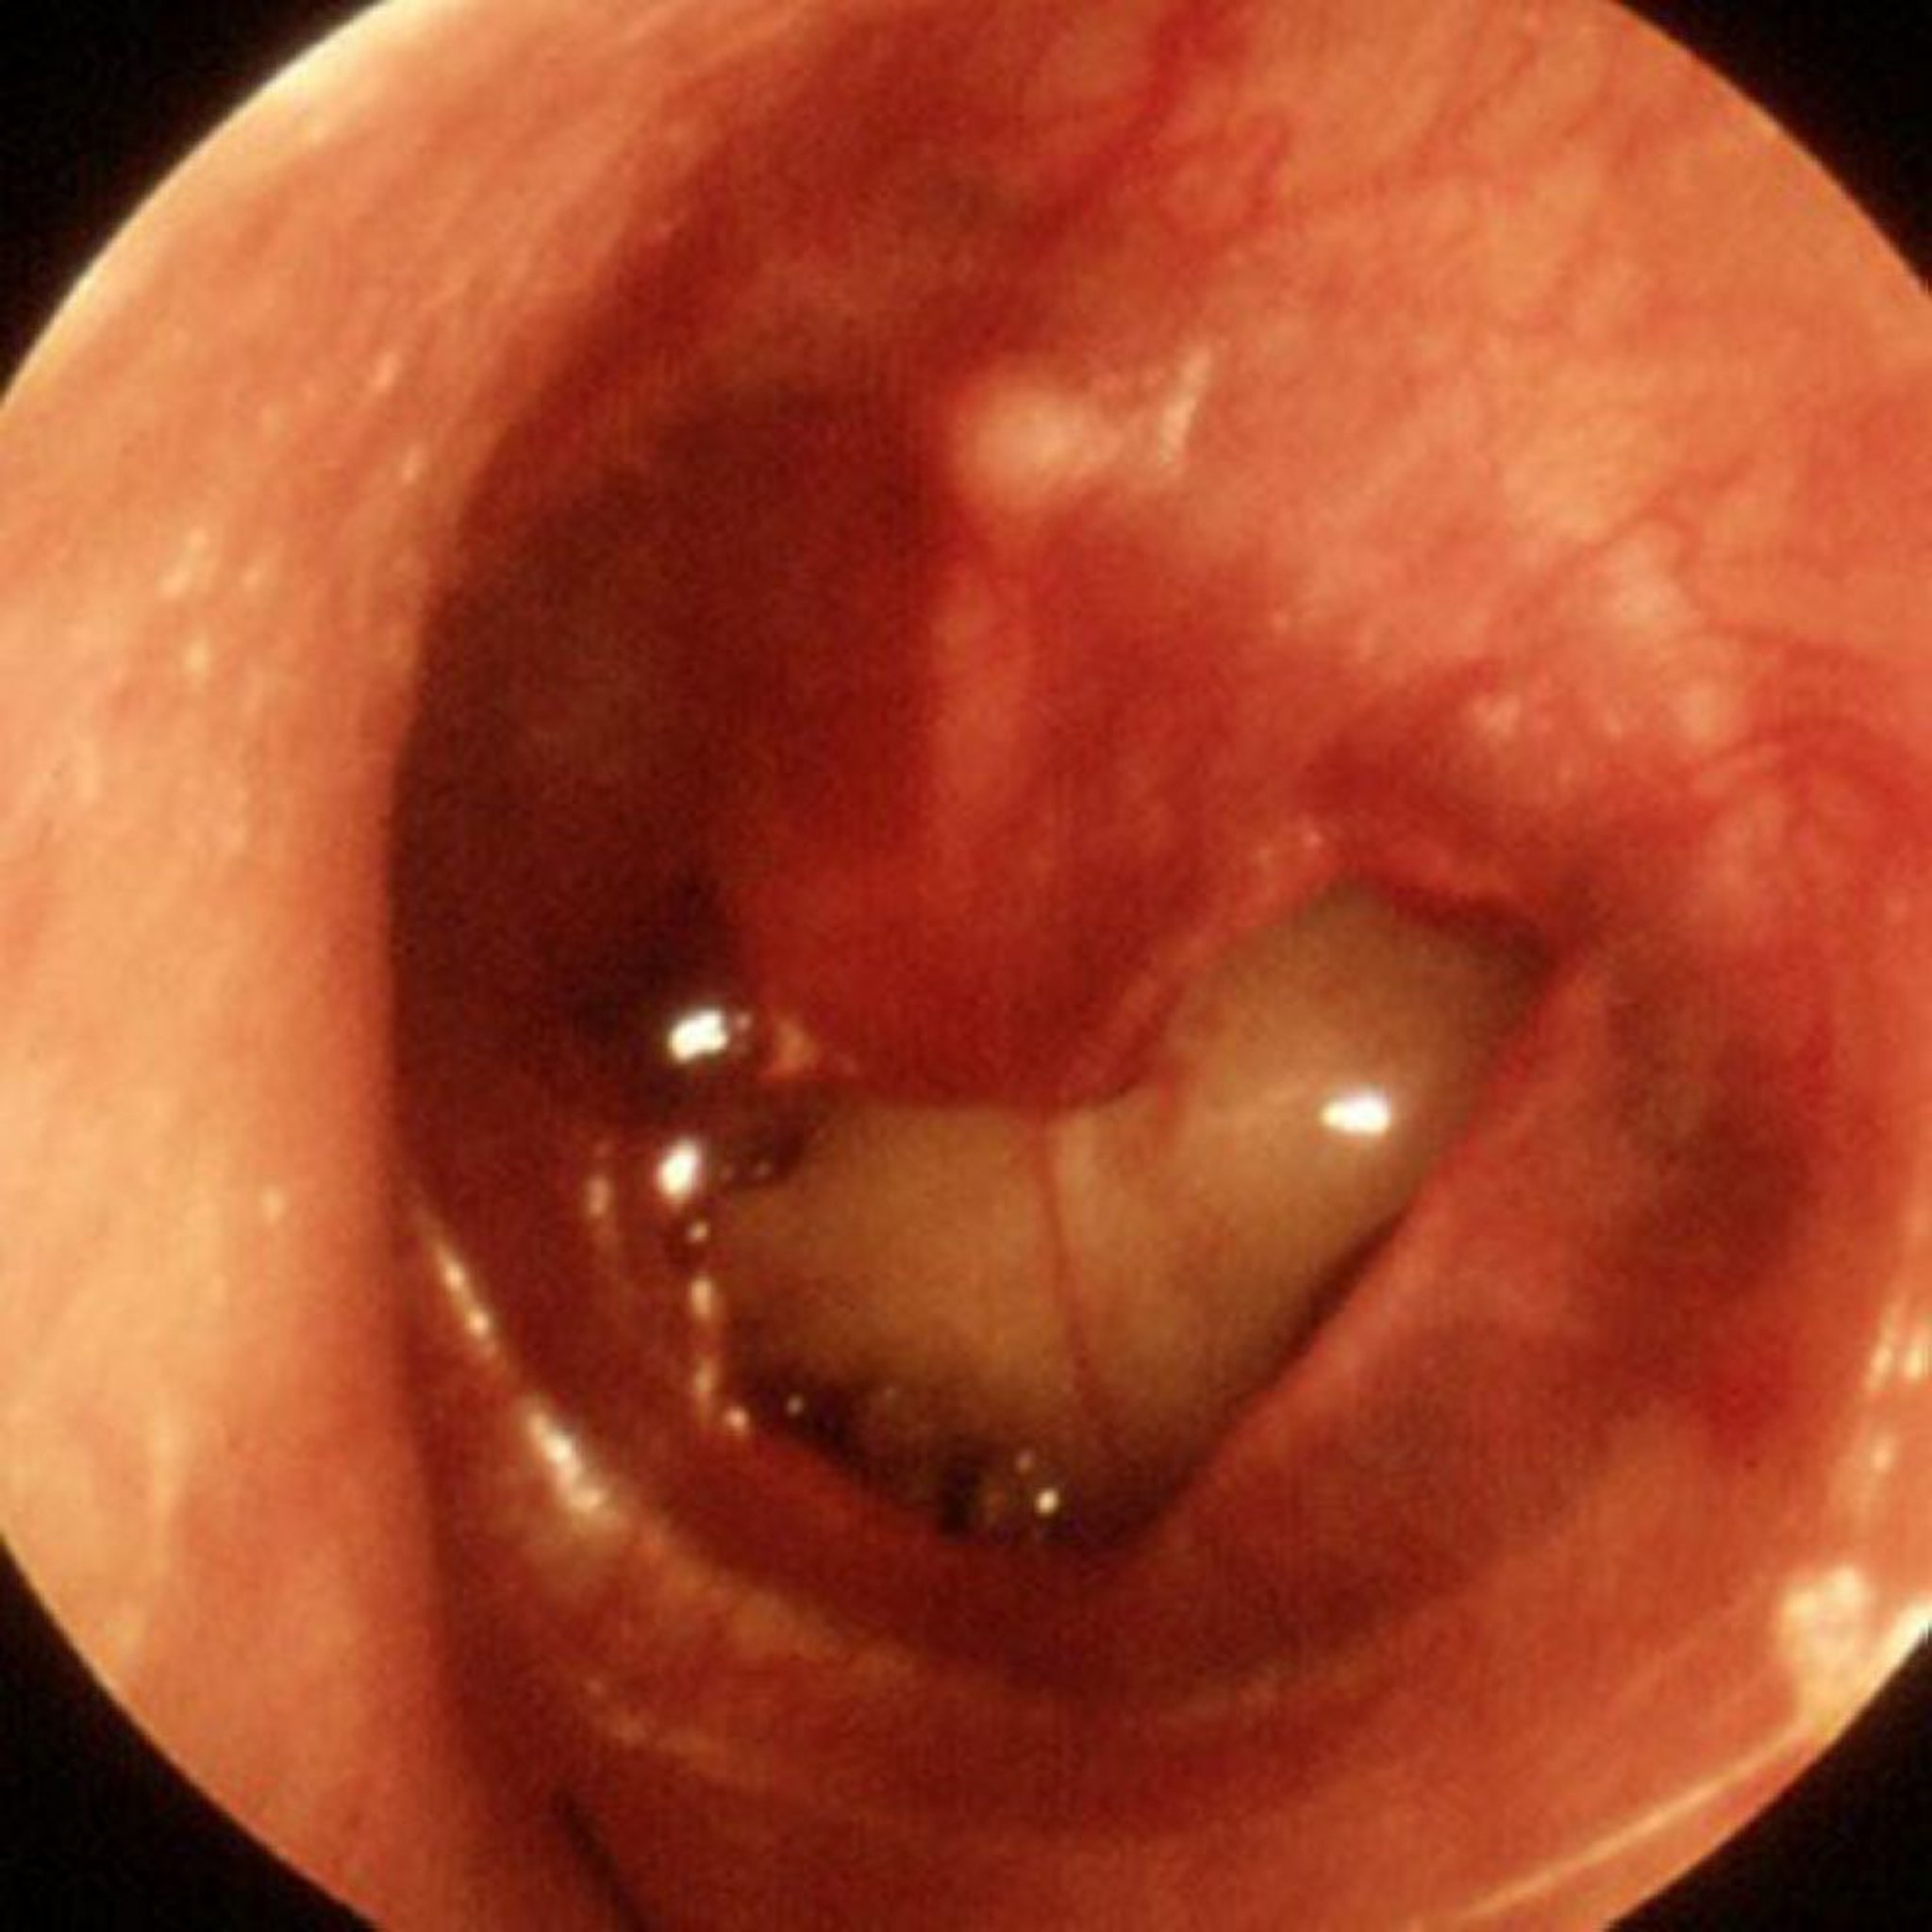

外傷性鼓膜穿孔

この画像では,外傷性の大きな穿孔が認められる。